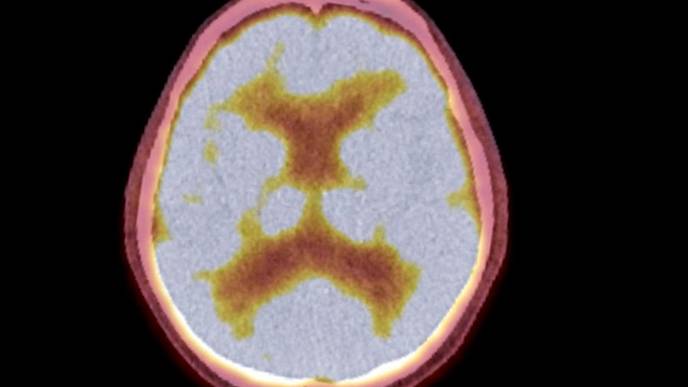

“What we like about the AMPET is that it moves with the head, and you can be in a real environment where you’re immersed and walk with it on,” she said. “What we demonstrated in the study is that when the patients walk, it’s not moving relative to the head and that’s what allowed us to get a relatively clean image. We also wanted to see what should be improved by us or other laboratories that are making these devices.”

“We observed brain activity in the parts of the brain that control leg movements when the patients walked, which was what we had hoped to see,” Brefczynski-Lewis said.